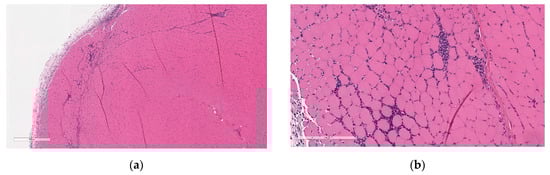

Microscopic findings at the injection sites included mixed cell inflammation and edema (Figure 5), which correlated with the macroscopic injection site findings. Inflammation at the injection site was characterized by large numbers of neutrophils with fewer plasma cells, macrophages, and lymphocytes admixed with abundant edema and small amounts of cellular debris, fibrin, and hemorrhage. Occasionally, inflammatory cells extend into the subcutaneous tissue/dermis of the overlying skin and into the extra-capsular tissue of the joint.

Figure 5.

Histopathologic features of Injection site inflammation and edema at the end of the dosing phase. (a) Injection site sections of BNT162b2 (V9) treated animals euthanized 2 days after the third dose (Day 17) showed inflammatory cells admixed with abundant pale eosinophilic fluid (edema) infiltrating and expanding subcutaneous tissue and connective tissue of skeletal muscle. (b) Higher magnification of (a) showing.

At the end of the 3-week recovery phase, there was complete resolution of the edema and partial recovery of the inflammation; the inflammatory cell infiltrate more chronic in nature, comprised primarily of lymphocytes, plasma cells, and macrophages, with few neutrophils (Figure 6).